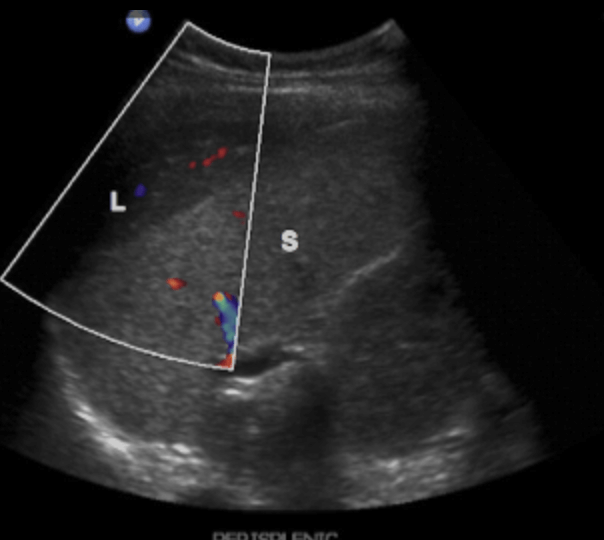

2. Long left lobe of the liver = Beaver tail liver

Beaver tail liver 좌엽이 길고 커져서 비장에 인접해 있다. 마치 비장의 피막하 혈종(subcapsular hematoma)처럼 보인다. 주로 마른 여자에서 확인된다.